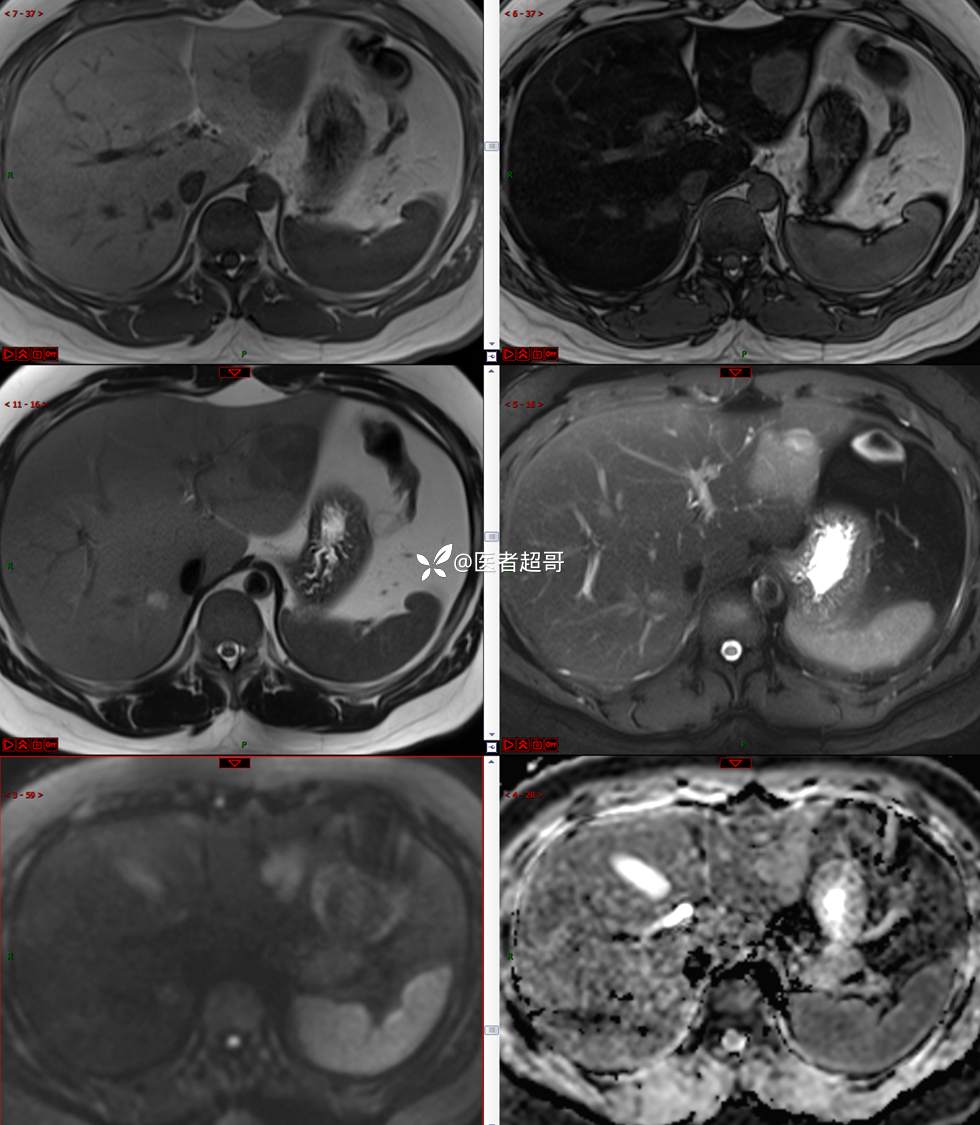

【影诊笔记685】男,31y,发现肝占位性病变5天就诊,请诊断分析,有病理结果!

主 诉:发现肝占位性病变5天。

现病史:患者缘于5天前体检时发现肝占位性病变,未予以特殊处置。现患者为求系统诊治就诊于我院,行普美显提示:肝左叶富血供占位,请结合临床及其他检查,肝多发血管瘤,脂肪肝,肝囊肿,请结合临床。门诊以“肝占位性病变”收入我科。病程中,饮食睡眠可,二便可,近期体重未见明显变化。